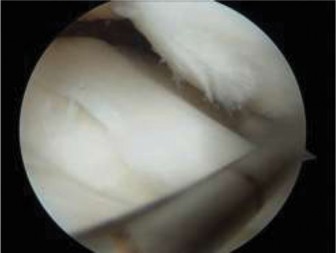

Clinical & Radiographic Imaging